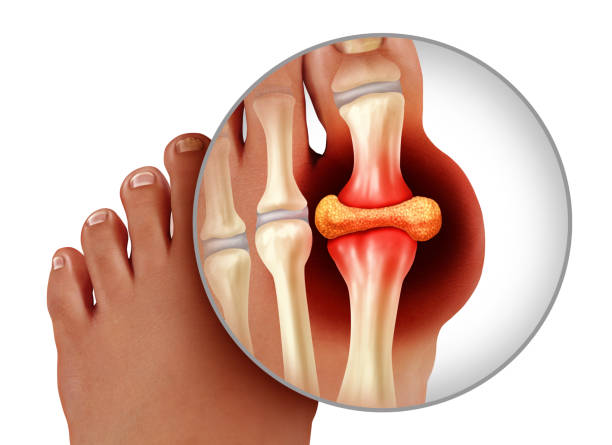

통풍 증상 원인과 관련하여 가장 많이 등장하는 물질은 ‘요산’으로 이 ‘요산’이 체내에 과다하게 쌓이면 통풍이 오게되는데 이 ‘요산’은 소변으로 나오는 산성물질이라는 의미로 고기나 생선류에서 많이 들어있는 필수아미노산 중 하나인 퓨린이 에너지로 사용되고 소변을 통해 찌꺼기 형태로 나가는 형태인데 적당한 시기에 체외로 배출을 하지 못한다면 이 요산과 나트륨이 결합하여 요산염 나트륨으로 화학적 결합을 하게됩니다.

이 화학적 결합은 체내 백혈구가 세균이나 바이러스로 인식해 잡아먹는데 이 과정에서 백혈구 안에 있는 염증 반응 물질을 터트리며 백혈구 속 염증 반응 물질이 지속적으로 터져 아주 심하게 염증과 통증을 느끼게 되는 것입니다. 따라서 우리 식습관과 밀접한 연관이 있는 통풍은 주로 새우젓, 동물내장 등 퓨린이 많은 들어간 음식을 즐긴다거나 맥주 등을 즐겨 요산 배출 장애가 발생하면 통풍에 걸리게 됩니다.